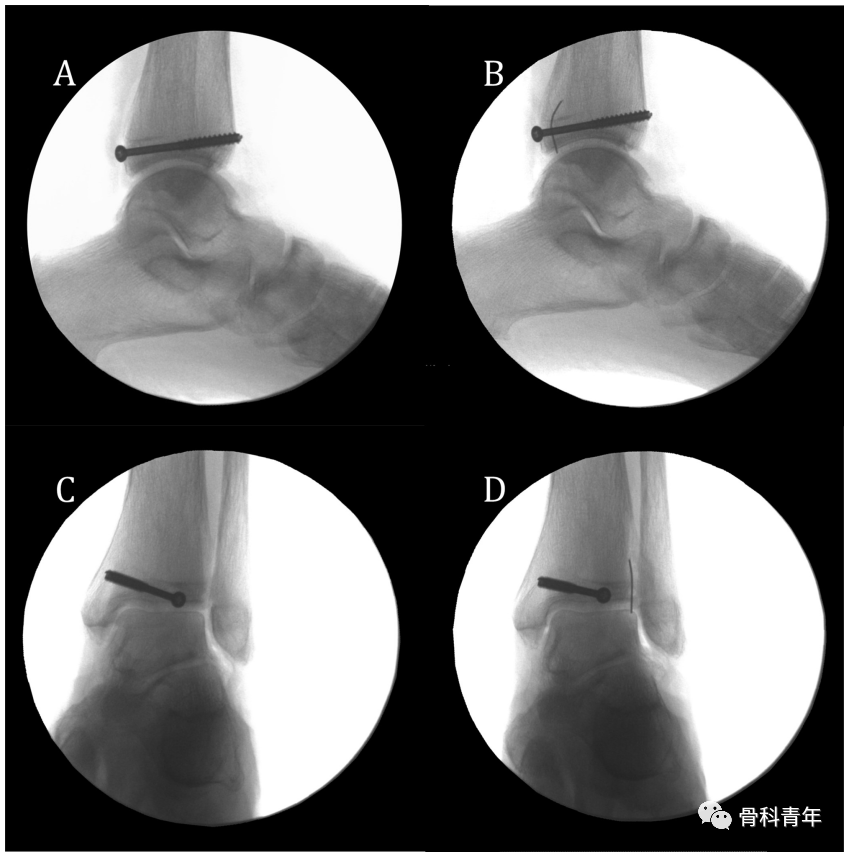

文章首先定义踝穴位PVSL(Posteromedial vertical syndesmotic line)线,该线为在踝穴位上,下胫腓间隙中胫骨后内侧皮质缘从后向前过渡的投影线

▲ 图示PVSL线与其在透视下的影像。

为了确定PVSL线是否可代表下胫腓间隙的内侧缘,研究者通过在下胫腓间隙内侧缘放置显影标识,并在该标识的内侧与外侧放置标识,以明确PVSL线是否易于辨别

该研究人员对10具标本进行了研究,9例标本螺钉未进入下胫腓内。典型如下:在侧位(A、B)与踝穴位(C、D)上,通过在PVSL线上放置不透光标识,可见后踝螺钉相对于标识的位置,D图上可见螺钉位于标识的内侧。

在一具标本中,后踝螺钉置入关节内,踝穴位上见后踝螺钉位于PVSL的外侧。